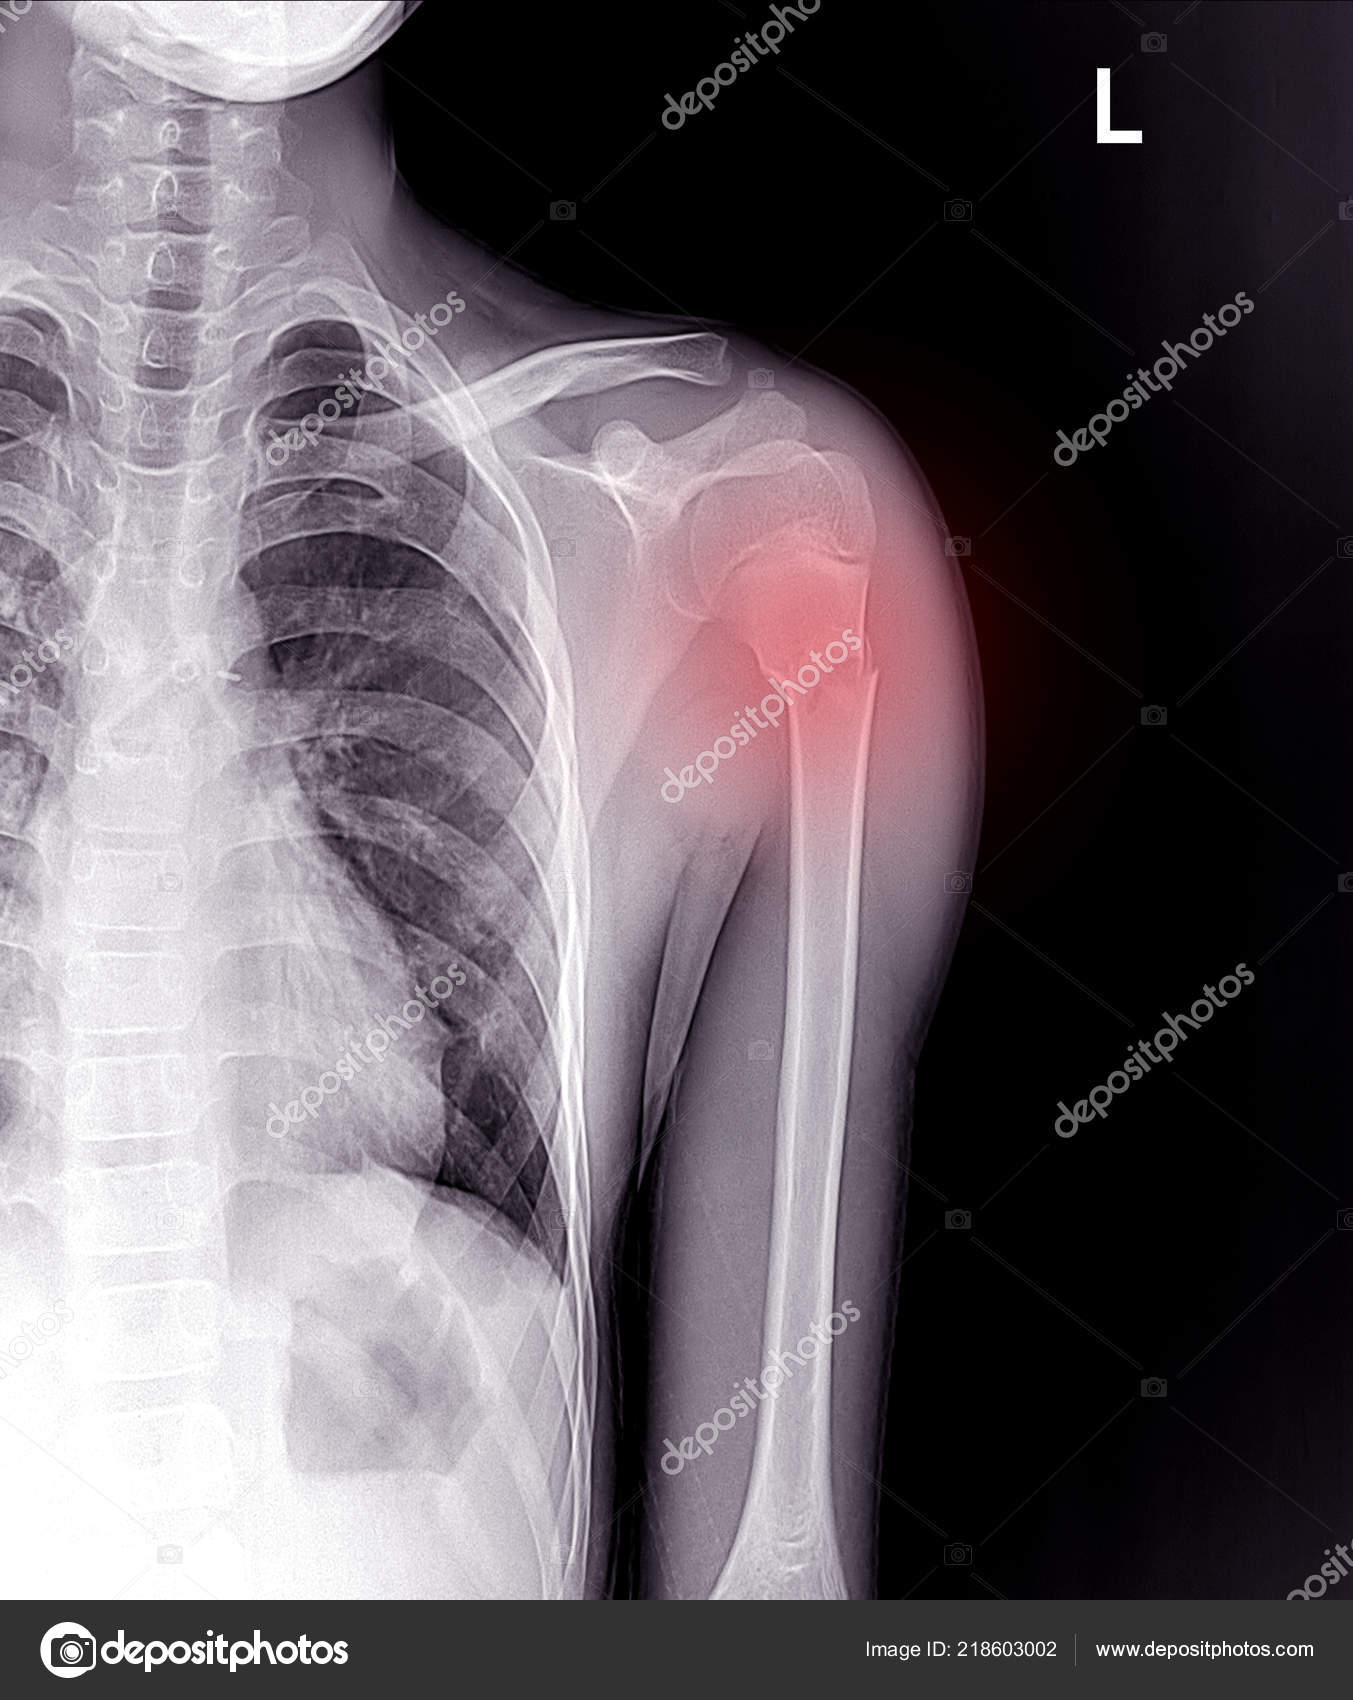

From depositphotos.com

Une Fracture Cou L'humérus Bras image libre de droit par Richmanphoto Humerus Bras De Fer Humeral shaft fractures are common fractures of the diaphysis of the humerus, which may be associated with radial nerve injury. Find out how a splint,. Learn how to perform plating of proximal and midshaft humeral fractures through the anterolateral approach. En haut à l’épaule avec la scapula (anciennement omoplate), en bas au coude. The neer system divides the proximal humerus. Humerus Bras De Fer.